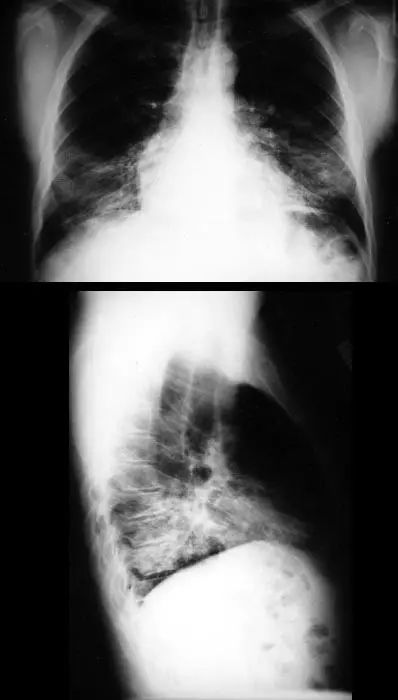

图1.3 细菌性肺炎。早期右肺中叶肺炎的影像学表现。

图1.4 53岁的严重军团菌肺炎患者。胸片显示双肺下叶致密实变。